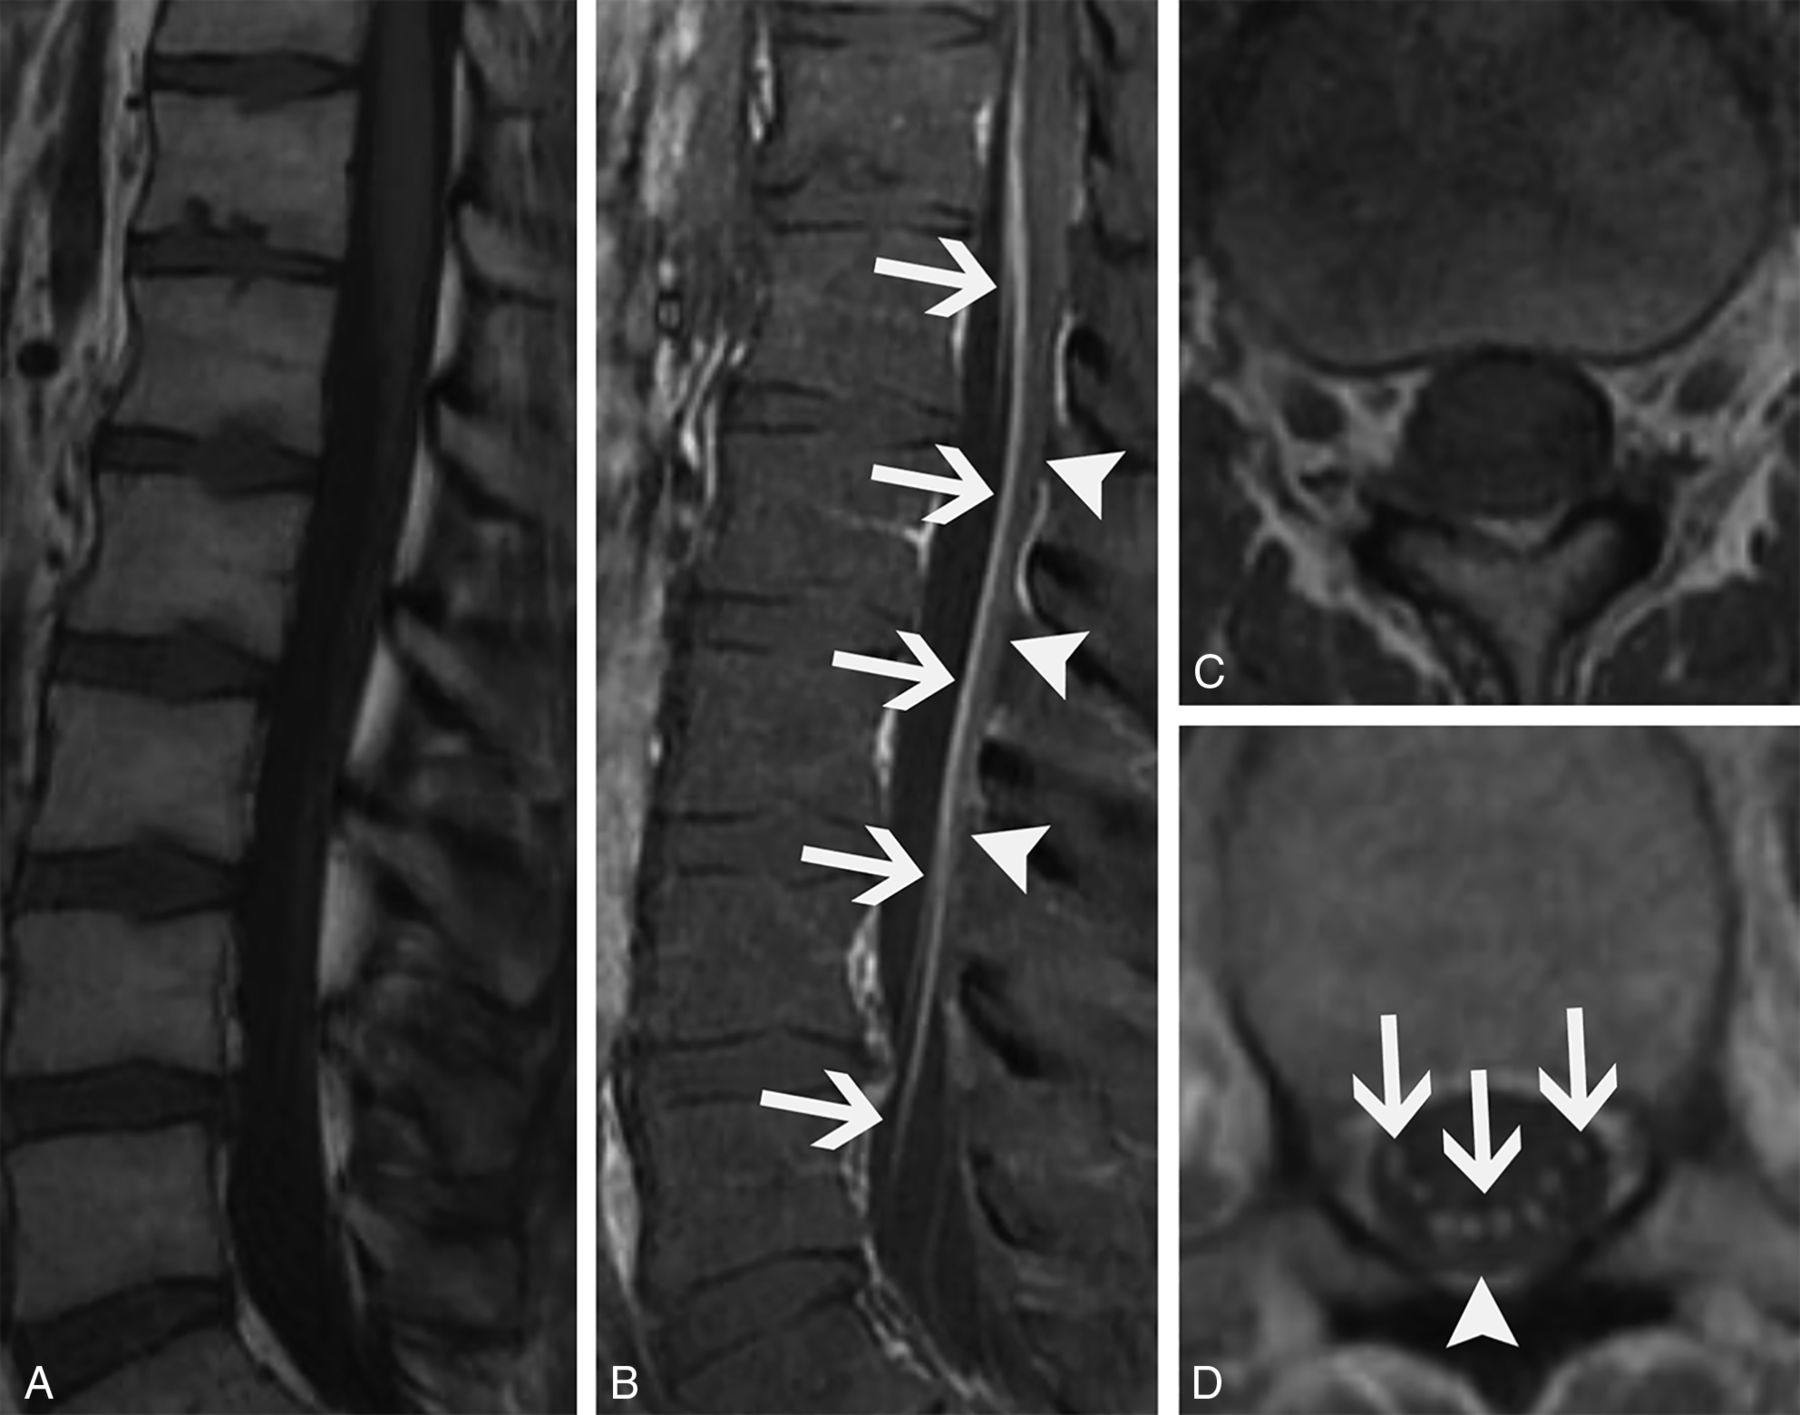

When confined to the spinal cord, imaging findings include longitudinally extensive T2 hyperintensity and enhancement (Fig 7). Tract-specific abnormalities, particularly along the lateral columns, are characteristic (Fig 7C, -G). Abnormal FDG uptake can also be present in the involved area of the spinal cord with this syndrome (Fig 7E), which could potentially be mistaken for metastatic tumor involvement.23 Differential considerations for this entity include neuromyelitis optica spectrum disorder, neurosarcoidosis, spinal dural AVF, radiation myelitis, and cord infarct. The presence of perimedullary flow voids usually suggests an AVF, whereas preferential involvement of the anterior horns often suggests cord infarct. Multiple sclerosis would not generally have longitudinally extensive involvement.

Paraneoplastic myelitis (A–E). A 52-year-old woman recently diagnosed with small cell lung cancer presented with progressive bilateral lower extremity weakness over weeks. Lumbar puncture was remarkable for elevated CSF IgG index and IgG synthesis rate, though no specific paraneoplastic antibody was identified. Sagittal T1-weighted pre- (A) and postcontrast (B) images and an axial postcontrast image (C) from her thoracic spine MR imaging show a long segment of enhancement involving the lateral columns of the thoracic spinal cord. Corresponding axial T2-weighted (D) and FDG-PET/CT (E) images show increased T2 signal (D, arrows) and marked abnormal FDG uptake (E, arrows) in the spinal cord. She was diagnosed with paraneoplastic myelopathy and had transient improvement with methylprednisolone. Paraneoplastic myelitis with treatment response (F–I). A 64-year-old woman recently diagnosed with small cell lung cancer presented with gait difficulties and progressive bilateral lower extremity weakness lasting several months. Serum and CSF were positive for CRMP5 autoantibodies. Sagittal T2-weighted (F) and axial T1-weighted postcontrast (G) images of the cervical cord show increased T2 signal (F, arrows) and enhancement of the lateral columns (G, arrows). She was treated with 6 months of cyclophosphamide and had partial symptomatic improvement. Follow-up sagittal T2-weighted image (H) shows near resolution of abnormal signal. There is mild residual patchy cord enhancement, greatest in the lateral columns (I, arrows).

In addition to the usual paraneoplastic work-up, MR imaging of the entire spine is particularly helpful in these patients because of the longitudinally extensive nature of spinal cord involvement. Imaging of the brain is also usually indicated to assess for associated encephalitis, which is frequently seen with anti-CRMP5 syndromes. Typical treatment includes management of the underlying malignancy and immunosuppression. Despite treatment, the outcome is overall poor with most patients becoming wheelchair dependent. Although follow-up of patients with paraneoplastic myelitis is not well documented in the literature, clinical improvement and improvement in imaging findings can occur (Fig 7F–I).